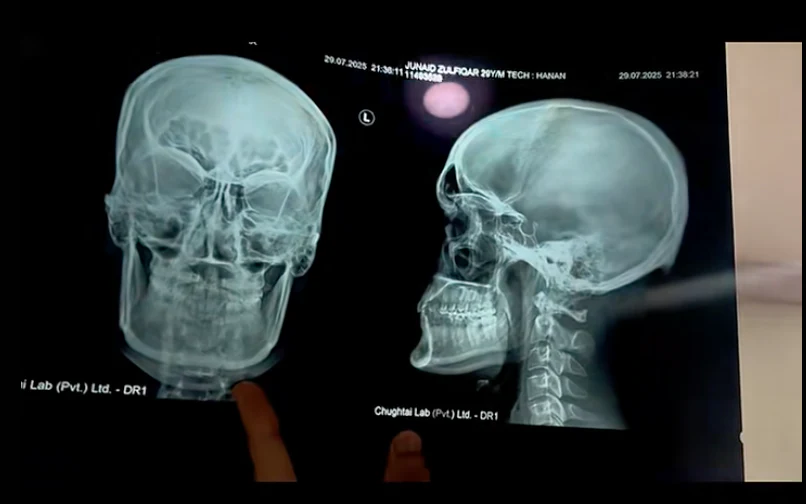

I went to the ortho a few days ago and they x-rayed my head and teeth and stuff and when I saw the xray I was surprised to see that my skull didn't look the way that I thought it would. I don't look recessed normally but when i saw my x-ray it looked like one of the three images just below.

When I look up "normal human skull x-ray" things like this pop up.

I think that if someone was looking at this from an aesthetic POV then they would say that this is either recessed or downward grown, especially the midface area, because it doesn't look super projected when you compare it to man-made replicas.

When I look up "normal human skull x-ray" things like this pop up.

I think that if someone was looking at this from an aesthetic POV then they would say that this is either recessed or downward grown, especially the midface area, because it doesn't look super projected when you compare it to man-made replicas.